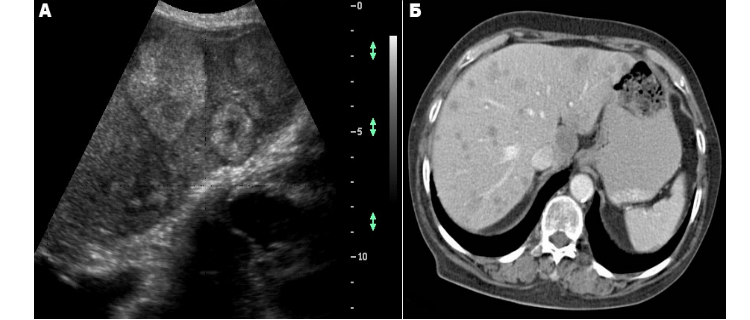

Профессия пациентки входит в спектр факторов риска из-за контакта с канцерогенами. Результаты диагностических тестов (УЗИ, КТ, цистоскопия с биопсией, анализ на онкомаркеры) оказались неутешительными – обнаружился рак мочевого пузыря с вторичным поражением печени. К сожалению, невзирая на курс терапии, больная умерла.

Среди методов, которые используются в современной диагностике вторичных опухолей печени, я могу назвать:

- УЗИ, или ультразвуковое исследование.

- Томография – магнитно-резонансная (МРТ), компьютерная, в том числе мультиспиральная (КТ, МСКТ), позитронно-эмиссионная (ПЭТ).